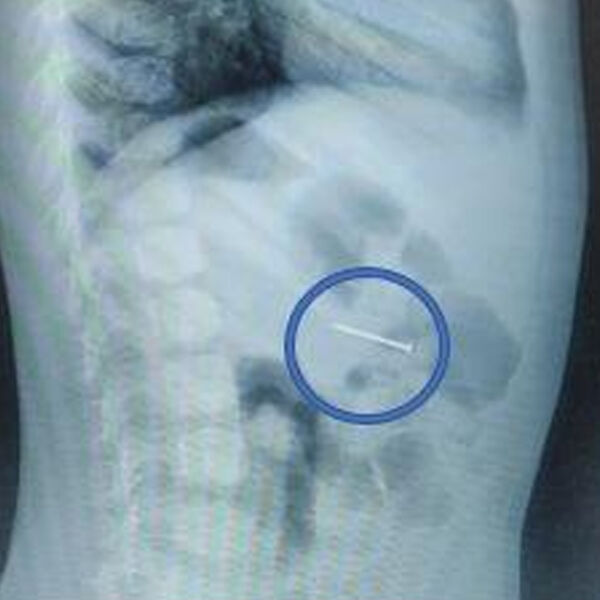

«Своевременно начатое вмешательство помогло избежать серьезных последствий. Сперва мы сделали рентгенографию – она подтвердила наличие гвоздя в желудке, а после выполнили гастроскопию: с помощью эндоскопических щипцов аккуратно захватили гвоздь за острый конец и извлекли его через ротовую полость», — поделился врач-эндоскопист Руслан Мусаев, добавив, что манипуляция заняла около 20 минут.